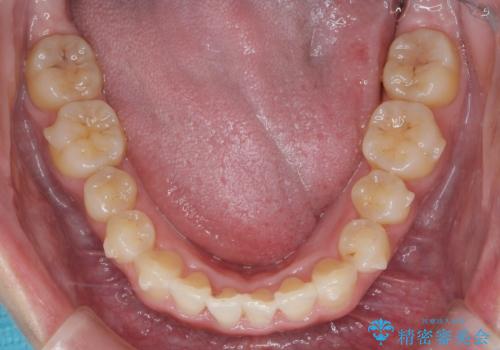

上下の歯のがたつきを改善するマウスピース矯正治療と、下顎に見られる大きな骨隆起を外科的に除去する治療計画を進めていきます。

歯並びが改善したとともに、骨隆起を除去したことで舌をしまうスペースも増え安定した口腔内環境を確立することができました。